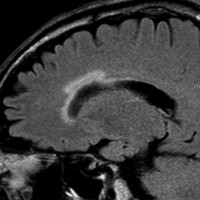

3歳の子どもの髄芽腫の放射線治療後に生じた脳萎縮

3歳の髄芽腫です。発症時から小脳表面や小脳橋角部を含めて転移がありました stage M2。化学療法で腫瘍はかなり縮小して,3歳7ヶ月まで頑張ってから,後頭窩照射 25.2グレイ14分割と脳脊髄照射 CSI 28.8グレイ16分割の放射線治療をしました。当時このような例では,脳脊髄照射 36グレイが標準治療でしたから,これでもかなり線量を落としました。

左側の画像は照射後4ヶ月目です。延髄の左側に放射線壊死が生じました。これは数ヶ月かかってゆっくり消褪しました。右側の画像は照射後1年くらいのものです。大脳白質にびまん性に萎縮性変化がみられます。典型的な放射線治療による白質萎縮です。この程度の線量でも脳壊死や全脳萎縮を生じない子どももいます。

放射線の副作用は同じ線量でも個人差がとても大きいです idiosyncrasy